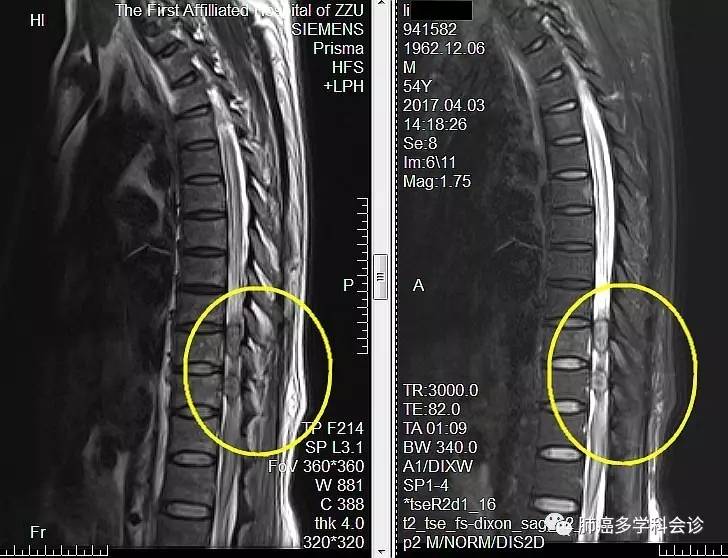

住院期间MRI:脑部未见明显异常,胸 9-11椎体水平脊髓内及胸10、11水平椎管右份异常信号。